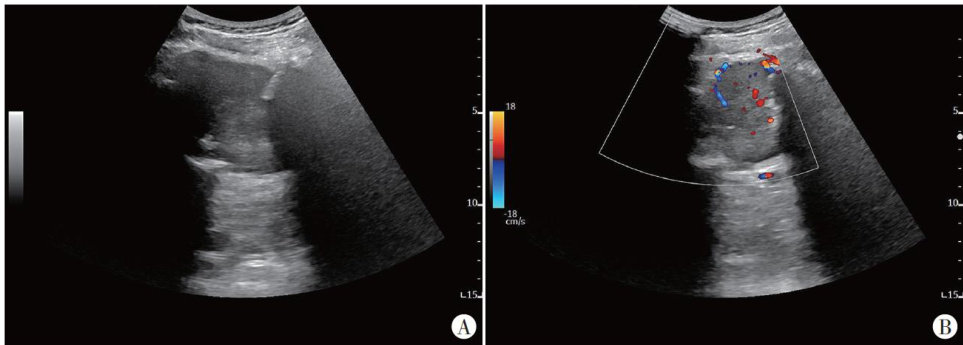

患者男,53岁,因“右臀部疼痛半年余"就诊,自述疼痛性质为间歇性钝痛。体格检查:骶尾部局部压痛、叩击痛,其余未见明显异常。外院MRI提示骶骨恶性肿瘤,甲状腺异常信号灶。我院超声检查:于骶骨旁见一大小约 62mm×59mm×44mm 实性低回声包块,形态不规则,边界欠清晰,包块局部边缘处可见粗大条弧样钙化,后方伴声影;CDFI于其内部可探及点条样血流信号(图1)。(剩余2769字)